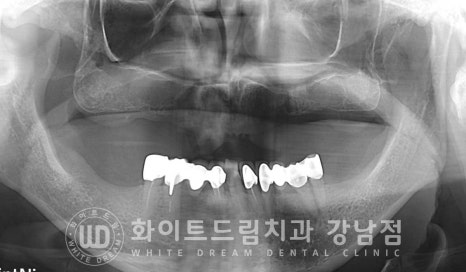

하악은 치아가 남아있는 상태이나, 상악 치아가 하나도 없으신 상태입니다.

특히 이전에 치아를 발치하게 된 이유가 '심각한 염증이지 않았을까'

라고 예상이 될 만큼 심한 잇몸뼈 소실을 보이는 상태였습니다.

구내 상악 사진을 보면 움푹 들어간 부분이 육안으로도 쉽게 확인될 정도로

골 소실이 심한 상태입니다.

이 상악 부위는 많은 양의 뼈이식이 필요할 것으로 예상되어

상악동 거상술식 중에서도 lateral, 측방 접근법을 이용하여

상악동을 크게 거상시킨 후 뼈이식을 진행해야 할 것으로 보였습니다.